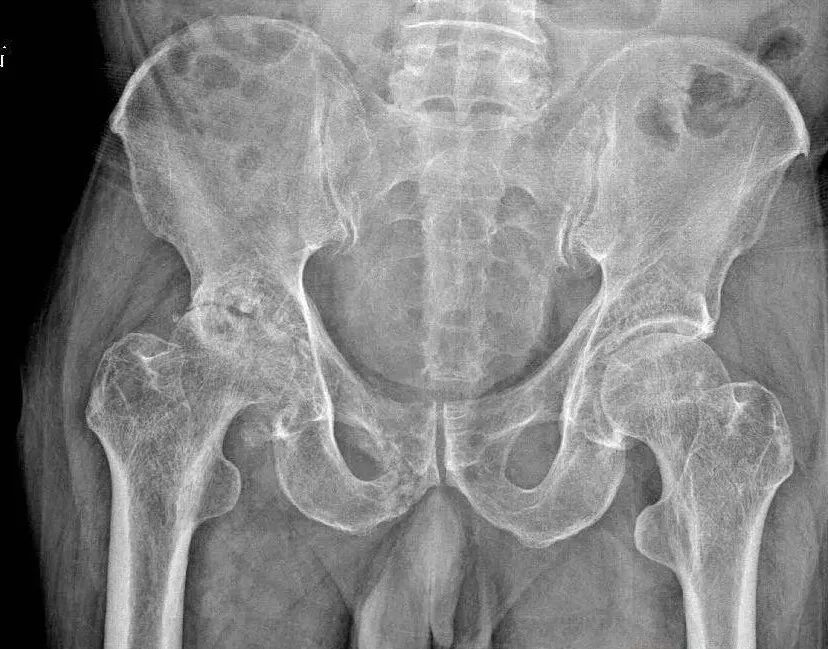

潘先生自青年时期便有每日饮酒的习惯,且饮酒量较大,最多能每日喝2斤白酒。近10年来,他逐渐感到右侧髋关节疼痛加剧,最终发展到无法行走的地步。经诊断,潘先生患上了“右侧股骨头无菌性坏死”,医生判断这与其长期过量饮酒导致的血脂异常、微循环障碍密切相关。

“酒精能伤肝肾,会抑制成骨细胞活性,加速骨质流失,同时影响股骨头供血,最终导致坏死。”镇江市中西医结合医院骨科副主任医师、科副主任王俊介绍,股骨头坏死晚期患者往往面临关节畸形、丧失活动能力的痛苦。而人工关节置换,是恢复功能的唯一有效手段。